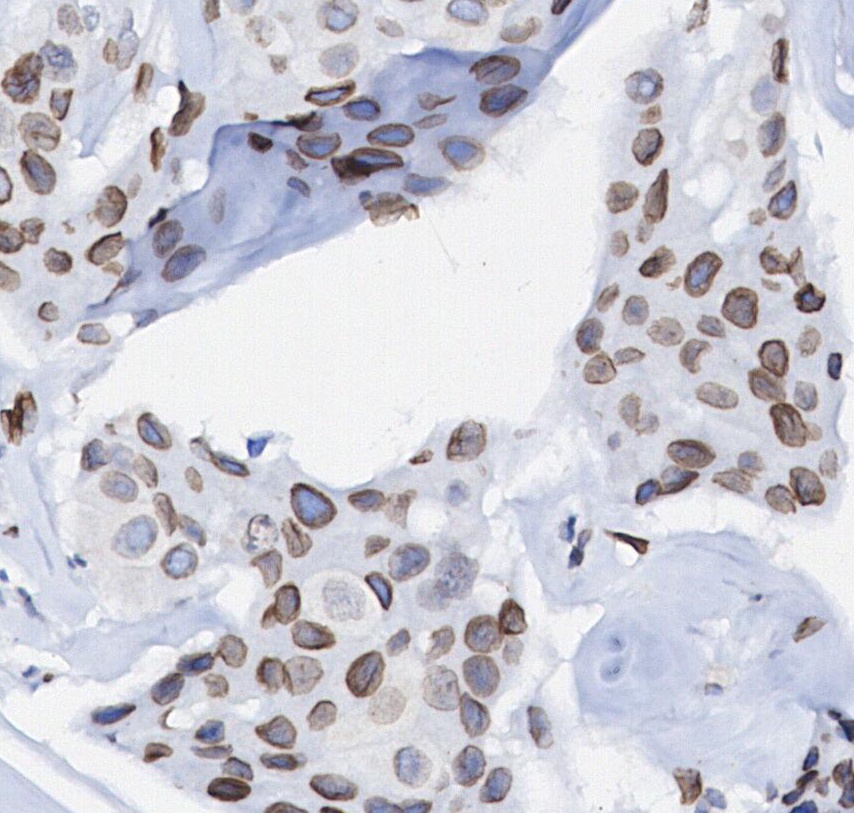

| IHC |

Experimental Protocol:

Deparaffinization/Rehydration

1. Deparaffinize/hydrate sections:

2. Incubate sections in three washes of xylene for 5 min each.

3. Incubate sections in two washes of 100% ethanol for 10 min each.

4. Incubate sections in two washes of 95% ethanol for 10 min each.

5. Wash sections two times in dH2O for 5 min each.

6.Antigen retrieval: For Citrate: Heat slides in a microwave submersed in 1X citrate unmasking solution until boiling is initiated; continue with 10 min at a sub-boiling temperature (95°-98°C). Cool slides on bench top for 30 min.

Staining

1. Wash sections in dH2O three times for 5 min each.

2. Incubate sections in 3% hydrogen peroxide for 10 min.

3. Wash sections in dH2O two times for 5 min each.

4. Wash sections in wash buffer for 5 min.

5. Block each section with 100–400 µl of blocking solution for 1 hr at room temperature.

6. Remove blocking solution and add 100–400 µl primary antibody diluent in to each section. Incubate overnight at 4°C.

7. Remove antibody solution and wash sections with wash buffer three times for 5 min each.

8. Cover section with 1–3 drops HRPas needed. Incubate in a humidified chamber for 30 min at room temperature.

9. Wash sections three times with wash buffer for 5 min each.

10. Add DAB Chromogen Concentrate to DAB Diluent and mix well before use.

11. Apply 100–400 µl DAB to each section and monitor closely. 1–10 min generally provides an acceptable staining intensity.

12. Immerse slides in dH2O.

13. If desired, counterstain sections with hematoxylin.

14. Wash sections in dH2O two times for 5 min each.

15. Dehydrate sections: Incubate sections in 95% ethanol two times for 10 sec each; Repeat in 100% ethanol, incubating sections two times for 10 sec each; Repeat in xylene, incubating sections two times for 10 sec each.

16. Mount sections with coverslips and mounting medium.

|

Btk Rabbit mAb recognizes endogenous levels of total Btk protein. |

Bruton’s tyrosine kinase (BTK) is a non-receptor tyrosine kinase that plays a key role in oncogenic signaling essential for the proliferation and survival of leukemic cells in various B cell malignancies. As one of the five members of the TEC family of non-receptor tyrosine kinases, BTK shares similarities with TEC and ITK, with all three proteins containing five distinct interaction domains: an amino-terminal pleckstrin homology (PH) domain, a proline-rich TEC homology (TH) domain, SRC homology domains SH2 and SH3, and a kinase domain responsible for enzymatic activity. BTK is primarily localized in the cytoplasm and is transiently recruited to the cell membrane through the interaction of its PH domain with phosphatidylinositol-3,4,5-triphosphate (PIP3), which is produced by phosphatidylinositol-3 kinase (PI3K). BTK activation occurs in a two-step process upon membrane recruitment, playing a crucial role in the B-cell receptor signaling pathway. This makes BTK essential for B-cell proliferation, differentiation, development, and survival. Dysregulated B-cell receptor signaling contributes to the pathogenesis of B-cell malignancies, making BTK an attractive target for therapeutic intervention. |